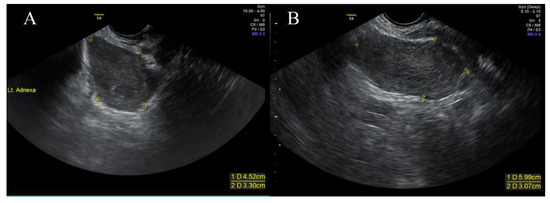

2. Case Presentation